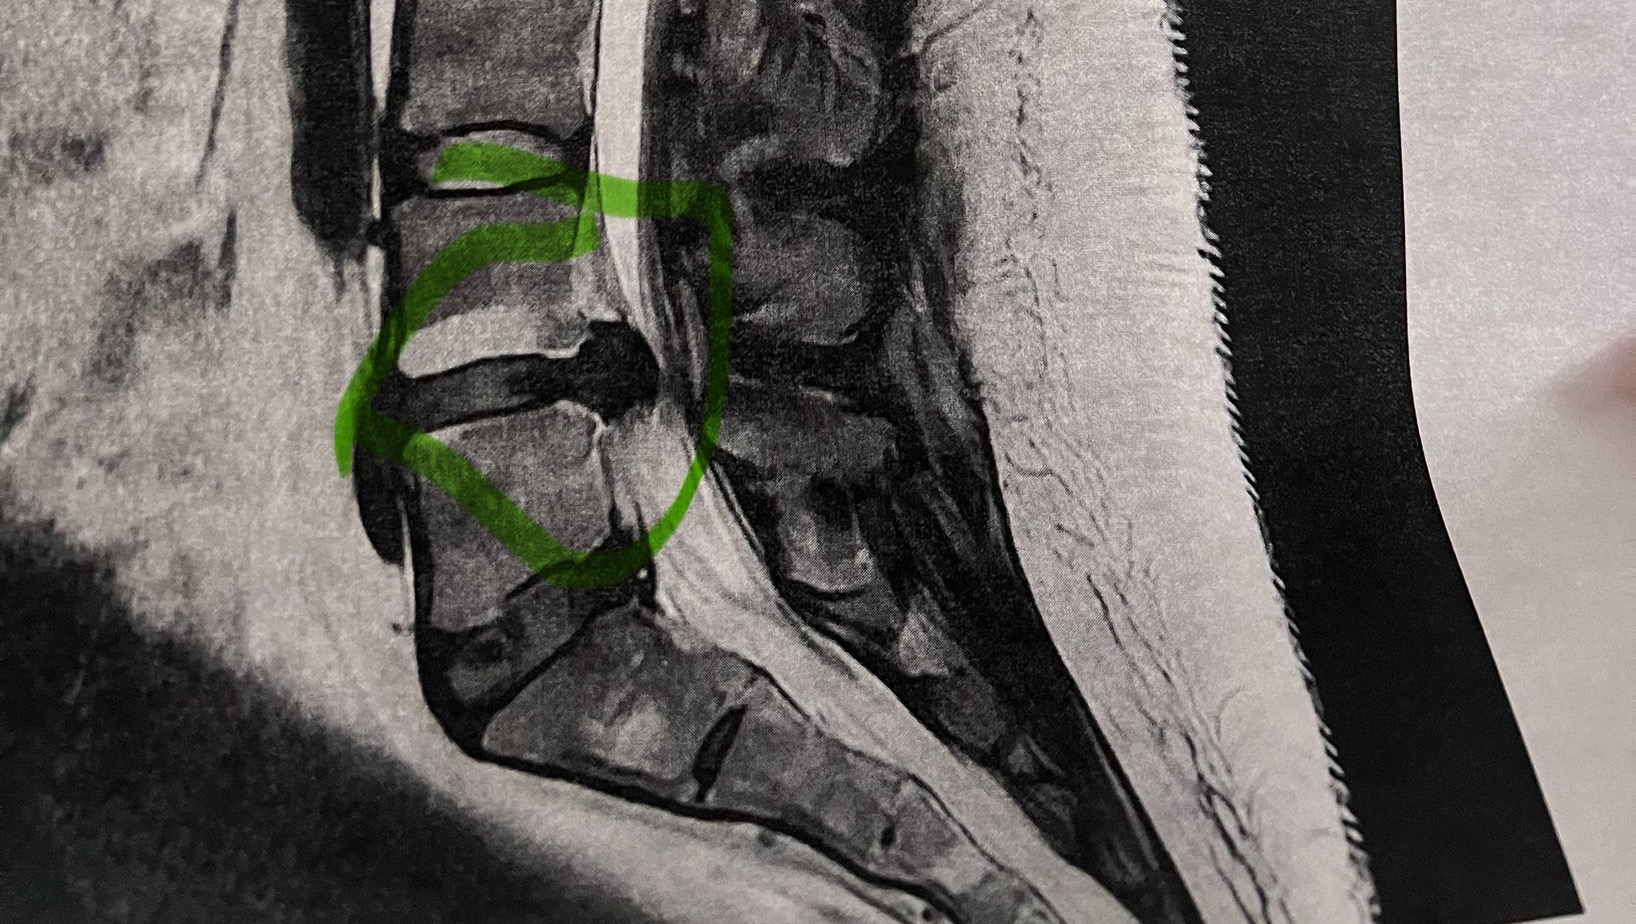

This has been a really difficult decision to come to but at this time my family and I are asking for your help. Through July Svetlana has been slowly losing the ability to sit, lay down, and walk without being in debilitating pain. She took all measures, going to her pcp, exercises, medication, urgent care, sleeping in the guest room, and sleeping on the floor to feel just an ounce of comfort. Unfortunately this all came to a head on Saturday June 12th. Svetlana was rushed to the hospital near home for back pain then transferred to another hospital because the first one she went to didn’t have an mri tech or neurosurgeon on staff. Once at the new hospital she waited 24 hours for a mri. That day her neurosurgeon said that typically with these injuries we would send a patient to PT and do pain management medication but in this case she will be needing a surgery LAMINOTOMY AND DISCECTOMY on her LEFT L4-L5 . After 48 hours of more pain she did receive that surgery on 7.14. Svetlana discharged from the hospital on 7.15 and has been slowly recovering at home. While recovering she started to get her benefits in order for short term disability and found out that she had less benefits through work than what she initially thought which is putting her between a rock and a hard place to go back to work earlier than anticipated to make ends meet. We all know that Svetlana is a strong fighter and will do whatever she can for her friends and family but this time she truly needs a break to heal. We are asking friends and family for help during this emergent and unpredictable time in our lives to donate if you can or to please share this post. Our goal of $2500 is to cover the unexpected loss of some amount of benefits that are already accruing as well as some days that she will not be paid while out of work. My family and I truly appreciate you all. Love everyone